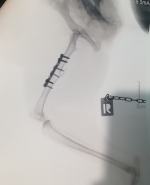

Do podobnego zdarzenia doszło 10 kwietnia w Grodkowie w godzinach wieczornych. Tym razem celem strzału na jednym ze spokojnych osiedli domków jednorodzinnych padł kot. - Kotek zadbany, z obrożą, codziennie przechadzał się po okolicy, po czym spokojnie wracał do swojego domu. Kilkuletni chłopiec- opiekun kota, nie może zrozumieć dlaczego postrzelono jego ulubieńca. Podczas operacji weterynarz wyciągnął z nogi kota pocisk typu DIABLO, który niestety uszkodził kość. Zwierzę miało złamanie strzępiaste trzonu kości udowej. Wdrożono kosztowne leczenie. Sprawa została zgłoszona na policję. Czy rasa ludzka upadła już tak nisko? - pisze czytelniczka.